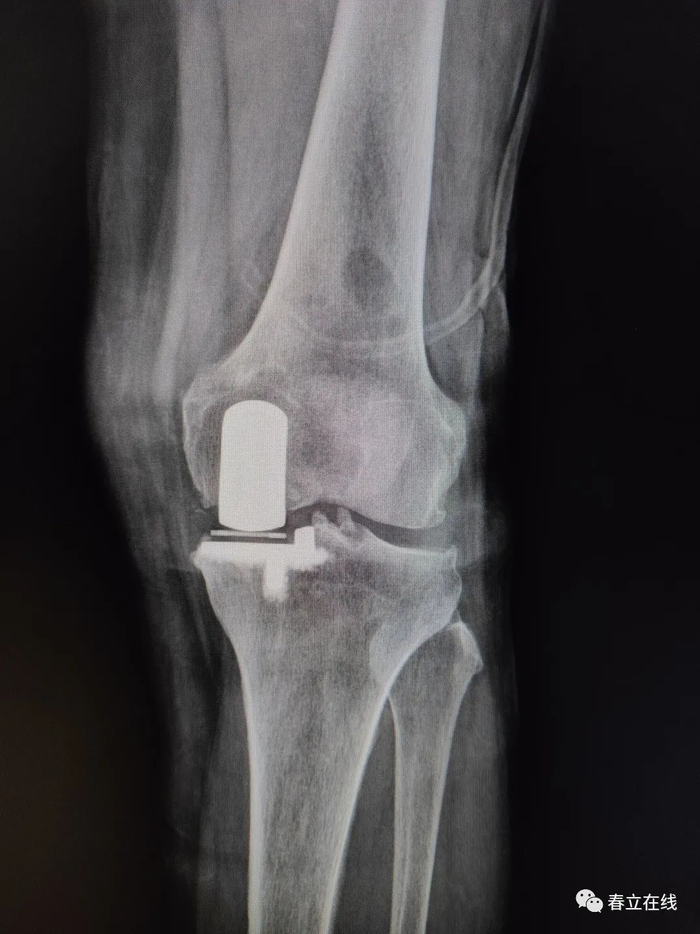

术后片